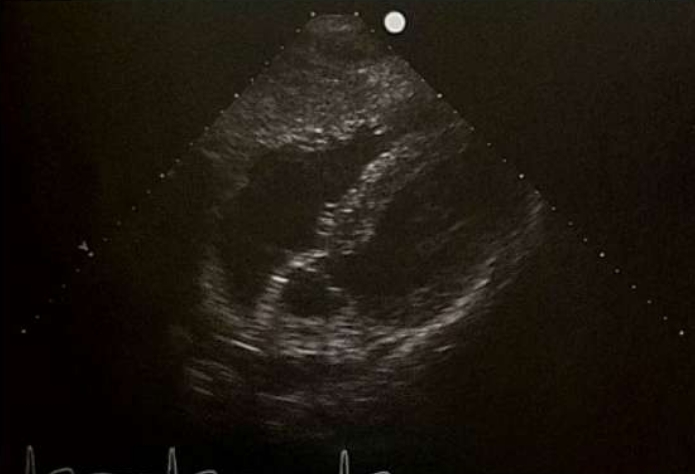

<p>What view is this?</p>

What view is this?

Apical 3 Chamber

<p>What view is being shown?</p>

What view is being shown?

Apical 4 chamber